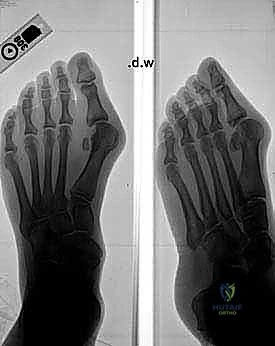

Effective preoperative planning is the cornerstone of a successful outcome. We evaluate a series of weight-bearing radiographs: AP and lateral views of the foot.

- Radiographic Analysis:

- Metatarsal Length: We assess the relative lengths of the metatarsals. Significant shortening of the first metatarsal can lead to transfer metatarsalgia postoperatively. While this osteotomy typically results in minimal shortening (average 0.98 mm), it's a factor to consider.

- Intermetatarsal Angle (IMA) and Hallux Valgus Angle (HVA): These are our primary measurements to quantify the deformity and guide the osteotomy's magnitude.

- Joint Congruency: We look for any subluxation or incongruity of the first MTP joint.

- Medial Eminence Size: This dictates the extent of our bunionectomy.

- Sesamoid Position: We note the lateral displacement of the sesamoids, which should ideally reduce with successful correction.

- Templating the Osteotomy: We routinely mark the proposed osteotomy directly on the radiograph. This allows us to visualize the wedge to be resected, its apex location, and the desired amount of correction. This mental rehearsal is invaluable.

FIG 2 • A–D. Preoperative and postoperative radiographs.